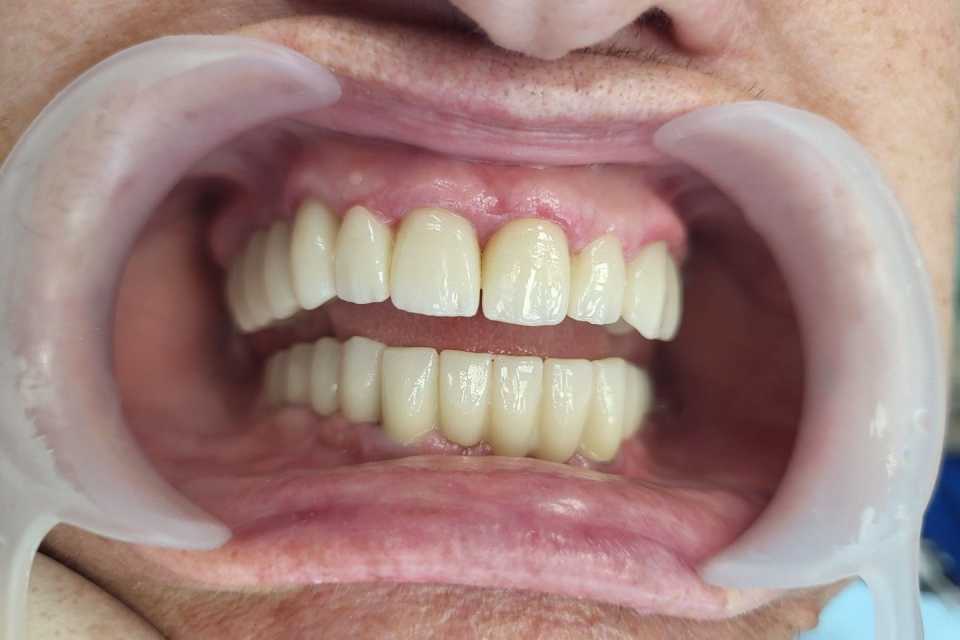

Planul de tratament a inclus extracția dinților parodontotici la nivelul mandibulei și inserarea a 5 implanturi dentare Mega-Gen AnyRidge cu conexiune multiunit, urmată de protezarea acestora cu o lucrare fixă, înșurubabilă, din ceramică pe suport de zirconiu.

La nivelul maxilarului, s-au efectuat extracțiile dinților parodontotici, tratamentul laser și chirurgical al leziunilor parodontale, urmate de reabilitarea protetică prin realizarea a două lucrări fixe din ceramică pe suport de zirconiu.